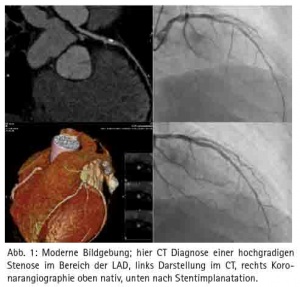

Brustkorbschmerzen gehört zu den häufigsten Einweisungsdiagnosen einer Notaufnahme, auch im Bundeswehrzentralkrankenhaus Koblenz. Seit 2010, rezertifiziert 2013, verfügt das Bundeswehrzentralkrankenhaus über eine Chest Pain Unit. Hier werden Patienten mit Brustkorbschmerzen optimal diagnostiziert und therapiert. Moderne Bildgebung stellt eine der wichtigen Säulen in der Diagnostik dar. Gerade in der Notaufnahme beginnt die suffiziente Untersuchung des Patienten mit einem im Bedarfsfall angezeigten triple-rule-out CT (Ausschluss signifikante KHK, Aortendissektion und Lungenarterienembolie in einer CT-Untersuchung) oder Koronar-CT (Abb. 1). Akute ST-Hebungsinfarkte werden gemäss den aktuellen Leitlinien (2014 ESC/EACTS Guidelines on myocardial revascularization) sofort ins Herzkatheterlabor verbracht und hier einer Koronarintervention mit Wiederöffnung des verschlossenen Koronargefäßes unterzogen. Diese therapeutischen Optionen müssen 24/7 angeboten werden, da viele kardiovaskuläre Notfälle sich außerhalb der regulären Dienstzeit ereignen, z. B. in den frühen Morgenstunden mit Aktivierung des sympathischen Nervensystems. Die Wiederherstellung der Reperfusion beim STEMI innerhalb der ersten 2 – 3 Stunden nach Symptombeginn muss unbedingt angestrebt werden. Jede Zeitverzögerung führt zu einer Prognoseverschlechterung. Im Idealfall wird das Herzkatheterteam bereits über den Notarztwagens bzw. die Rettungsleitstelle informiert, so dass beim Eintreffen eines NAW’s der Patient direkt ins Herzkatheterlabor verbracht werden kann und eine Wiedereröffnung der Koronargefäße erfolgt. Wenn ein Patient mit einem akuten ST-Hebungsinfarkt sich ohne Rettungsmittel direkt in der Notaufnahme vorstellt, ist eine door-to-ballon (Zeit zwischen betreten der Notaufnahme und Wiedereröffnung des Herzkranzgefässes im Herzkatheterlabor) unter einer Stunde anzustreben. Nur in Ausnahmefällen, wie z. B. im Auslandseinsatz sollte die Thrombolysetherapie noch als alternative Therapie wegen schlechterer Wiedereröffnungsraten des Koronargefäßes mit höheren Komplikationsraten durchgeführt werden. Gemäß den gültigen Leitlinien ist auch bei erfolgreicher Thrombolysetherapie eine zeitnahe Koronarangiographie anzustreben, da aufgrund des rupturierten Plaques nur der adhärente Thrombus durch die Thrombolysetherapie beseitigt wird und bei unveränderter Plaquemorphologie ein hohes Reinfarktrisiko besteht. Auch bei Patienten mit einem NSTEMI (Nicht-ST-Hebungsinfarkt), der sich prognostisch langfristig kaum von dem Risiko eines ST-Hebungsinfarktes unterscheidet, ist eine zeitnahe Koronarangiographie anzustreben, insbesondere wenn die Patienten hämodynamisch instabil sind, einen relevanten Troponinanstieg (bevorzugt werden sollte das hochsensitive Troponin), dynamische ST- oder T-Wellenveränderungen im Ruhe-EKG aufweisen oder der Grace score (http://ww.gracescore.org) über 140 liegt. Insbesondere beim STEMI (ST-Streckenhebungsinfarkt) kann eine additive Thrombusaspiration über einen speziellen Herzkatheter bei großer Thrombuslast im verschlossenen Koronargefäss hilfreich für eine erfolgreiche Reperfusionsstrategie sein (Abb. 2).